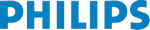

Функции для кардио-исследований

- Fetal Heart Navigator - функция для навигации сердца плода